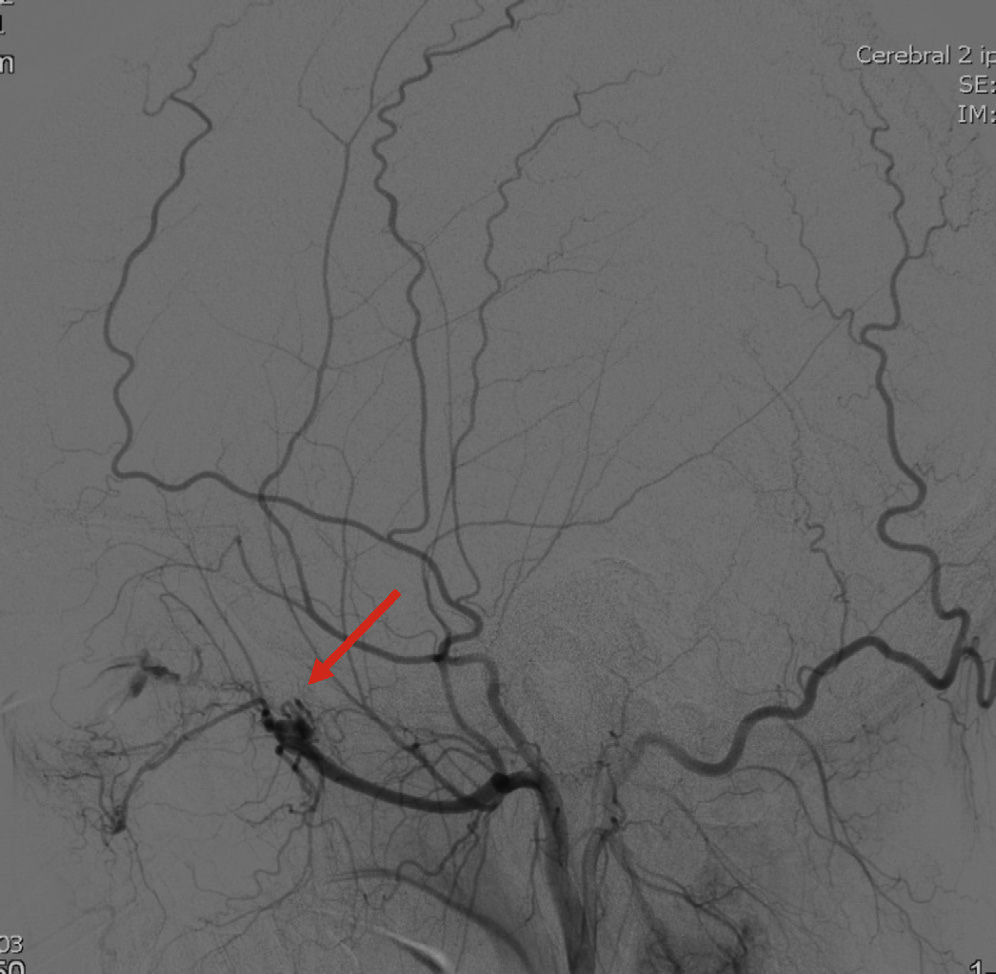

The case of a 21-year-old male with a history of left proptosis and diplopia of two weeks of onset is presented. The MRI showed an ethmoid-orbital vascular lesion with anterior skull base invasion and orbital extension. Biopsy of the ethmoid confirmed fibrovascular tissue, which supported the diagnosis of angiofibroma.

It is a benign neoplasm with local characteristics of malignancy due to its ability to invade adjacent areas. In this case, the debut presented with manifestations of orbital extension. A broad and multidisciplinary approach is needed in order to improve prognosis.